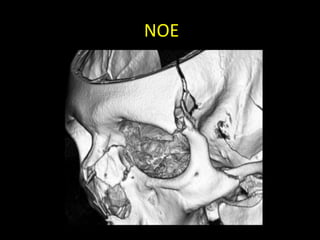

FRACTURA NASO-ÓRBITO-ETMOIDAL

(NOE)

• Golpe en nariz y transmisión posterior

etmoidal (contrafuertes maxilares mediales)

• Fractura del tercio medio facial que involucra

hueso etmoides (lámina perpendicular,

papirácea y cribiforme), propios nasales y

apófisis ascendentes de maxilares.

• Es la zona de la cara con menor resistencia a

fuerzas de fractura.

NOE

• Clasificación de Markowitz

– Tipo I: segmento central único, sin compromiso del

canto interno.

– Tipo II: segmento central conminuto, sin compromiso

del canto interno.

– Tipo III: segmento central conminuto, con

desinserción del canto interno.

FRACTURA NASO-ÓRBITO-ETMOIDAL (NOE) • Golpeen nariz y transmisión posterior etmoidal (contrafuertes maxilares mediales) • Fractura del tercio medio facial que involucra hueso etmoides (lámina perpendicular, papirácea y cribiforme), propios nasales y apófisis ascendentes de maxilares. • Es la zona de la cara con menor resistencia a fuerzas de fractura.

NOE • Clasificación deMarkowitz – Tipo I: segmento central único, sin compromiso del canto interno. – Tipo II: segmento central conminuto, sin compromiso del canto interno. – Tipo III: segmento central conminuto, con desinserción del canto interno.

• #18 The Markowitz and Manson classification system categorizes fractures of the NOE complex according to whether the medial canthal tendon is involved, as follows: In type I NOE fractures, the medial canthal tendon is intact and connected to a single large fracture fragment; in type II fractures, the fracture is comminuted, and the medial canthal tendon is attached to a single bone fragment; in type III fractures, comminution extends to the medial canthal tendon insertion site on the anterior medial orbital wall at the level of the lacrimal fossa, with resultant avulsion of the tendon (Figs 6, 7) (14). Although the tendon itself is not visible at multidetector CT, the radiologist’s report of the degree of comminution of the medial orbital wall at the level of the lacrimal fossa may be helpful for surgical planning of medial canthal tendon repair. Figures 6, 7. (6) Three-dimensional CT images of an adult skull with graphic overlays depict the Markowitz and Manson classification system for classifying fractures of the NOE complex: type I NOE fracture (a), characterized by a single large central fragment with attached medial canthal tendon; type II NOE fracture (b), characterized by comminution without extension to the medial canthal tendon attachment; and type III NOE fracture (c), characterized by comminution through the medial canthal tendon attachment, with resultant tendon avulsion. (7) Three-dimensional CT image of the left medial maxillary buttress in lateral oblique orientation shows a single fracture fragment that includes the lacrimal fossa at the expected insertion site of the medial canthal tendon, findings indicative of a type I NOE fracture. Fractures through the left frontal calvaria, lateral orbital rim, and zygomatic arch also are seen.

• #20 comminuted fracture of the NOE complex with telecanthus and involvement of the bilateral lacrimal fossae (arrows), findings indicative of a type III fracture of the NOE complex with medial canthal tendon avulsion. A fragment of the fractured right medial orbital wall impinges on the right optic nerve